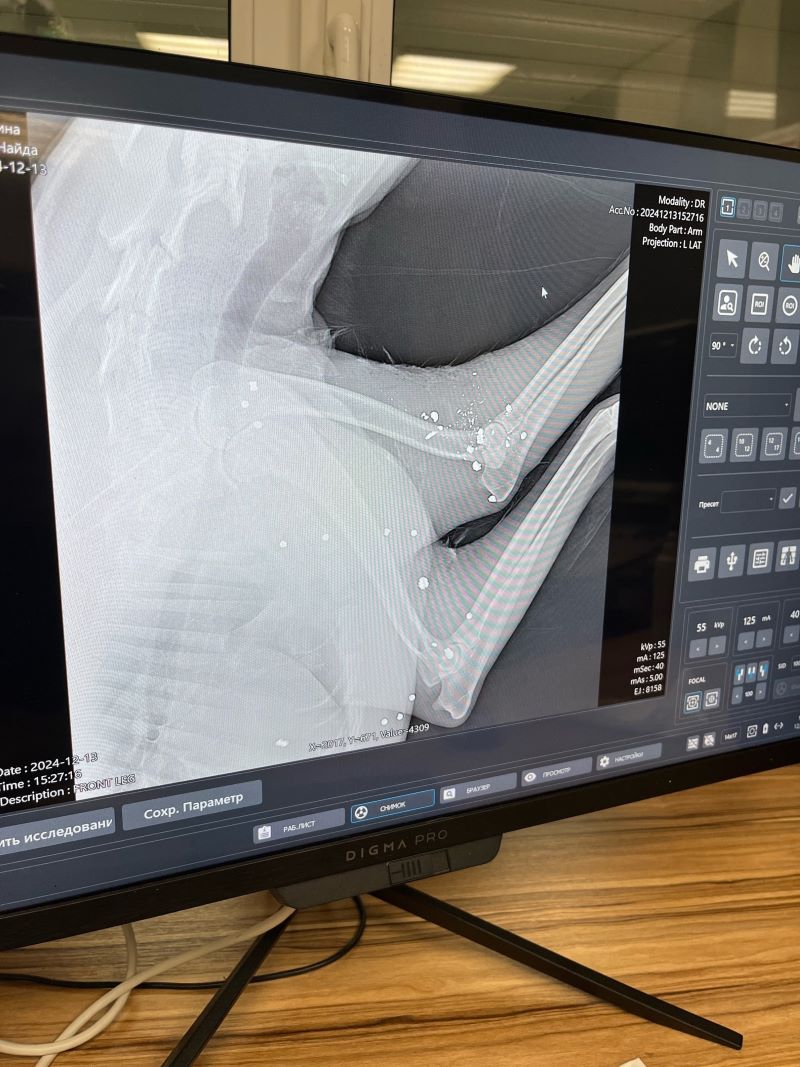

В редакцию портала« маленькая Сызрань» обратилась женщина, которая сообщила о страшном инциденте. В пятницу, 13 декабря, примерно с 10.00 до 12.00 в районе села Троекуровка неизвестным из оружия была расстреляна собака. По предварительной версии, это был охотник, который стрелял с дороги. Собака, которая живет в поселке с рабочими не была безнадзорной, но по стечению обстоятельств именно в этот день она выбежала на трассу и оказалась на обочине. Как сообщила автор, рентген показал, что тело собаки испещрено пулями. У собаки остались щенки. Автор сообщила, что сельчане намерены написать заявление в полицию.

Фото: фото предоставлены порталу Маленькая Сызрань Данилой М.